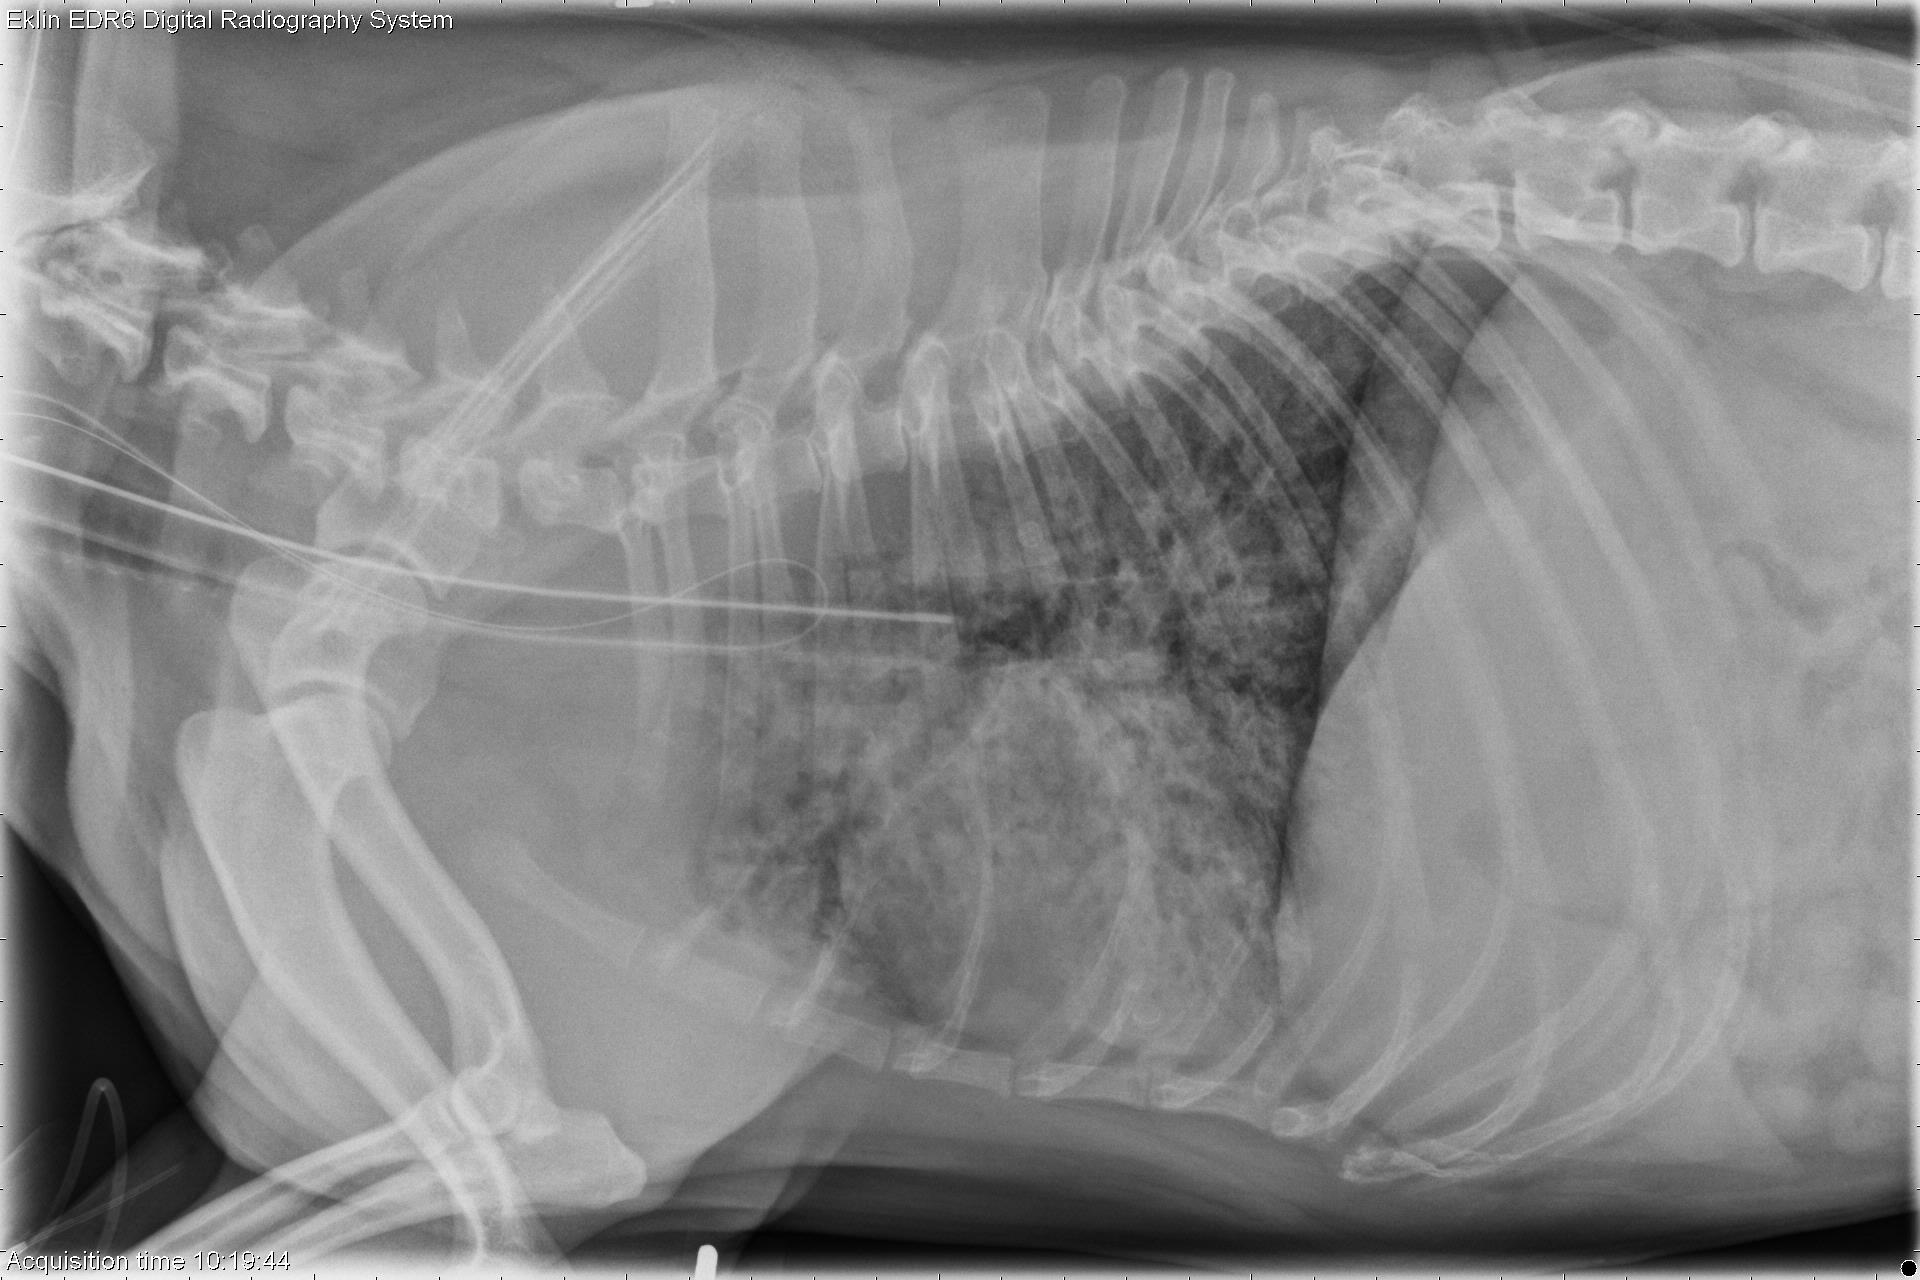

Pneumonia Rad Dog coughing, Kennel, Cough How Long Does Dog Pneumonia Cough Last Your dog’s pneumonia can last a. Treatment lasts approximately two weeks but may be extended if needed. If there is an underlying cause for the pneumonia, such as a neurologic condition increasing risk of aspiration, your pet’s recovery will depend on. How long does a kennel cough vaccine last? The kennel cough vaccination is designed to last about 12 months.. How Long Does Dog Pneumonia Cough Last.